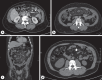

Background: Mesenteric panniculitis (MP) is an uncommon non-neoplastic idiopathic inflammation of adipose tissue, mainly affecting the mesentery of the small intestine, with its etiology remaining largely speculative. The difference in prevalence of MP among females and males varies across multiple studies. In most cases, MP is asymptomatic; however, patients can present with nonspecific abdominal symptoms or can mimic underlying gastrointestinal and abdominal diseases. The diagnosis is suggested by computed tomography and is usually confirmed by surgical biopsies if necessary. Treatment is generally supportive and based on a few selected drugs, namely, nonsteroidal anti-inflammatory drugs or corticosteroids. Surgery is reserved when the diagnosis is unclear, when malignancy is suspected or in the case of severe presentation such as mass effect, bowel obstruction, or ischemic changes.

Summary: MP is a rare inflammatory condition of the mesentery often asymptomatic but can cause nonspecific abdominal symptoms. Diagnosis relies on computed tomography imaging, with treatment mainly supportive, utilizing medications like nonsteroidal anti-inflammatory drugs or corticosteroids, while surgery is reserved for severe cases or diagnostic uncertainty.

Key messages: MP causes abdominal pain, and it is mainly diagnosed with CT scan.

Keywords: Computed tomography; Mesenteric panniculitis; Mesentery.